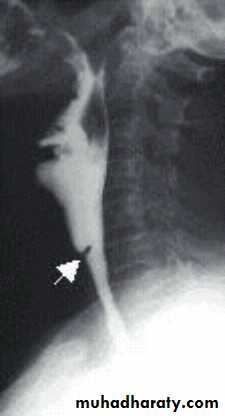

Contrast films: barium swallow is needed in the diagnosis of pharyngeal pouch, esophageal web and hypopharyngeal mass.

A chronic atrophic type of inflammation of the mucous membrane of the pharynx. The major changes occur in the postcricoid region initially started by fissuring and hyperkeratosis followed by fibrosis, web formation of stricture.

• -Haematological: CBP---- hypochromic microcytic anaemia, low serum iron and high iron binding capacity.• -Ba -swallow: web at the

• postcricoid region.

• The condition should not be diagnosed until an organic lesions has been excluded in order not to miss an early carcinoma.• -Ba -Swallow ---- cricopharyngeal spasm